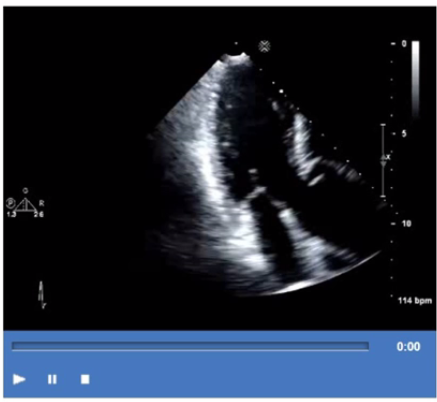

Which mitral regurgitation jet direction is most consistent with hypertrophic obstructive cardiomyopathy?

In hypertrophic obstructive cardiomyopathy (HOCM), systolic anterior motion (SAM) of the anterior mitral leaflet causes posteriorly directed mitral regurgitation (MR) jets. The abnormal anterior leaflet motion leads to incomplete leaflet coaptation and regurgitant flow directed toward the posterior left atrium.

Anterior jets are seen with posterior leaflet abnormalities. Central jets are seen in functional MR. Medial jets are less common and depend on leaflet pathology.